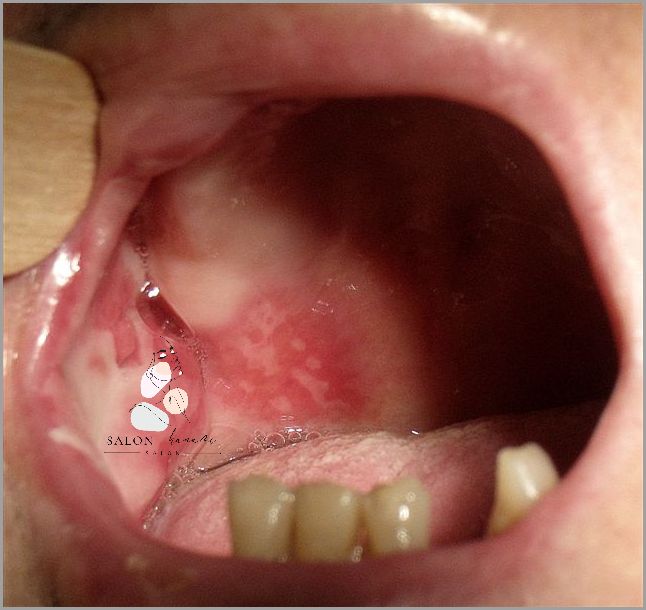

Zapalenie jamy ustnej to stosunkowo powszechna choroba, która dotyka ludzi w każdym wieku. Zwykle wywołuje je infekcja bakteryjna lub wirusowa, która wpływa na błony śluzowe jamy ustnej. Występowanie zapalenia jamy ustnej może być spowodowane przez niewłaściwe dbanie o higienę jamy ustnej, czynniki dziedziczne, infekcje wirusowe, zmiany hormonalne lub nadużywanie pewnych produktów. Objawy zapalenia jamy ustnej mogą się różnić, w zależności od rodzaju infekcji, ale najczęstsze z nich to ból i pieczenie w jamie ustnej, zaczerwienienie i obrzęk dziąseł, białe lub żółte plamki na języku lub błonach śluzowych, a także obecność krwi w ustach lub nieprzyjemny zapach.

Zapalenie jamy ustnej jest stanem zapalnym wywołanym przez szereg zarazków lub bakterii. Może być również wywołane przez alergeny lub inne czynniki drażniące. Objawy zapalenia jamy ustnej są bardzo charakterystyczne, obejmując ból i swędzenie, obrzęk i zaczerwienienie, a także tworzenie się pęcherzyków w jamie ustnej. W zależności od rodzaju zapalenia jamy ustnej, leczenie może obejmować zarówno leki przeciwbakteryjne, jak i leki przeciwhistaminowe.